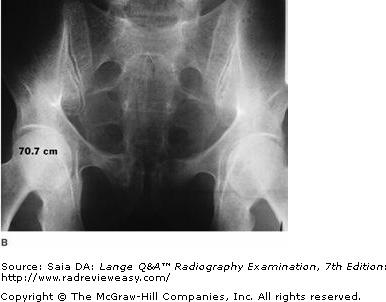

Which of the following statements is (are) true regarding the images below?

- Image A was made using a higher kilovoltage than image B.

- Image A was made with a higher-ratio grid than image B.

- Image A demonstrates shorter-scale contrast than image B.

C 2 and 3 only

-Image A was made using 80 kV at 75 mAs; image B was made using 100 kV at 18 mAs; all other exposure factors remained the same. As kilovoltage is increased, the percentage of scattered radiation relative to primary radiation increases—hence, the grayer appearance of image B. Use of optimal kilovoltage for each anatomic part is helpful in keeping scatter to a minimum. The production of scattered radiation also will be limited if the field size is as small as possible. A grid is the most effective way to remove scattered photons from those exiting the patient. Grids are designed to selectively absorb scattered radiation while absorbing as little of the useful beam as possible. Images produced with higher-ratio grids are likely to evidence the effect of less scattered radiation than those made with lower-ratio grids.